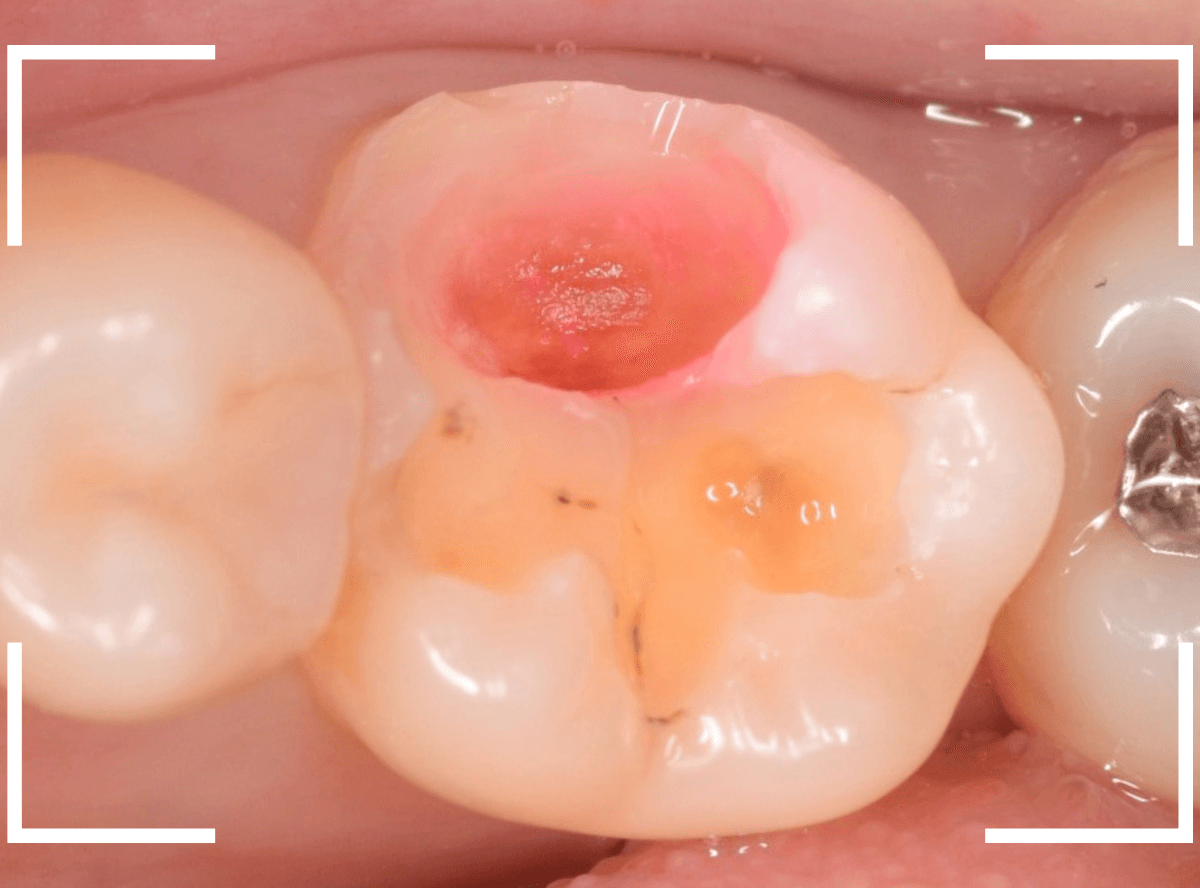

慎重に全ての虫歯を除去したところです。

〇部が神経の入り口が見えているところです。

神経を保護する処置をして、しばらく経過観察しますが、痛みが出て神経を除去する必要が出る可能性も高いです。

痛みが出ませんように・・・。